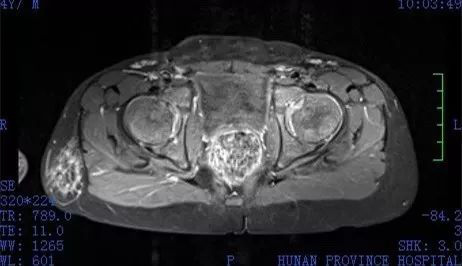

在湖南省人民医院儿六科和泌尿三科,徐璇主任和段燚星主任共同分析皓皓的情况,经过染色体复查、基因检测以及腹部生殖系统增强磁共振检查、腹腔镜探查术,皓皓只有一套男性的生殖系统,没有子宫、卵巢及卵睾等器官及组织,但男性外生殖器发育较差,染色体结果仍然显示是正常女性的染色体,基因检测也显示为女性。